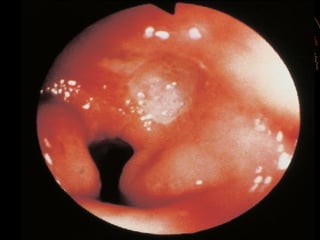

Chronic peptic ulcer.

Acute gastric

erosions.